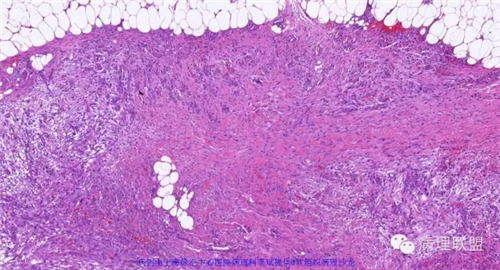

年轻人,最好发上肢,病程短,结节状增生,无明显包膜。镜下分带状,中央少细胞粘液变,周边细胞丰富,可见胶原化。大量增生的梭形细胞可呈席纹状。其间常可见淋巴细胞浸润和红细胞渗出,偶见多核巨细胞。

主要病理表现:粘液、水肿性纤维组织增生基础上,散布各阶段的肌成纤维细胞、成纤维细胞,侵袭周围正常的纤维脂肪组织,所以病变整体状态呈星芒状。